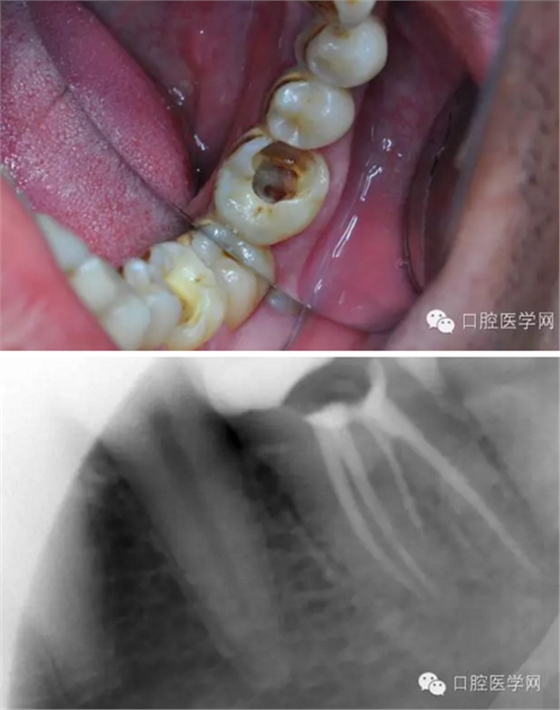

下面我來分享一下我近期的一個鈣化根管病例:

患者,肖某,男,32歲,#36慢性牙髓炎。遠(yuǎn)中舌根根尖1/3彎曲而且鈣化不通,我用盡辦法疏通了很久也沒到達(dá)WL,(我一直在幻想,要是有超聲系統(tǒng)該多好,可是現(xiàn)實很骨感,我們單位暫時還沒有超聲系統(tǒng)),后來我放棄了,最后的根充片顯示遠(yuǎn)中舌根充填物距根尖端2.84mm,屬于欠填范圍(根管內(nèi)充填物距根尖端2mm以上),其它三根根尖1/3鈣化相對沒那么嚴(yán)重,根充片顯示屬于恰填范圍(根管內(nèi)充填物距根尖端0.5~2mm)。歡迎網(wǎng)友們針對這個病例提出寶貴的建議!